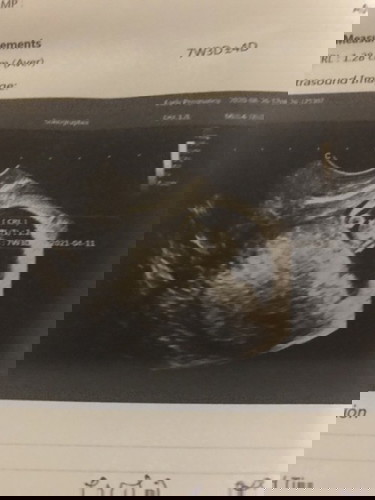

อุลตร้าซาว์ครั้งแรก พบถุงตั้งครรภ์ อายุครรภ์ 4 สัปดาห์ แล้วเมื่อวานอุลตร้าซาว์อีกครั้งพบว่าอายุครรภ์ 7 สัปดาห์ พบถุงไข่แดง แต่หมอไม่พบการเต้นของหัวใจ หมอนัดให้มาดูอีก2สัปดาห์ หากหมอไม่พบการเต้นของหัวใจ หมอบอกว่าต้องขูดมดลูก ตอนนี้ควรทำยังไงดี กังวลไปหมดเลยค่ะ น้องจะยังอยู่มั้ยคะ หรือ ควรรอให้อายุครรภ์เท่าไหร่ค่ะ เพื่อให้แน่ใจว่าหากไม่พบสัญญาณการเต้นของหัวใจ นั้นแสดงว่า เสียน้องไปแล้วจริง (ก่อนหน้านี้มีเลือดสีน้ำตาลออกนิดหน่อย ไม่ได้ออกทุกวันนะคะ) ขอบคุณค่ะ